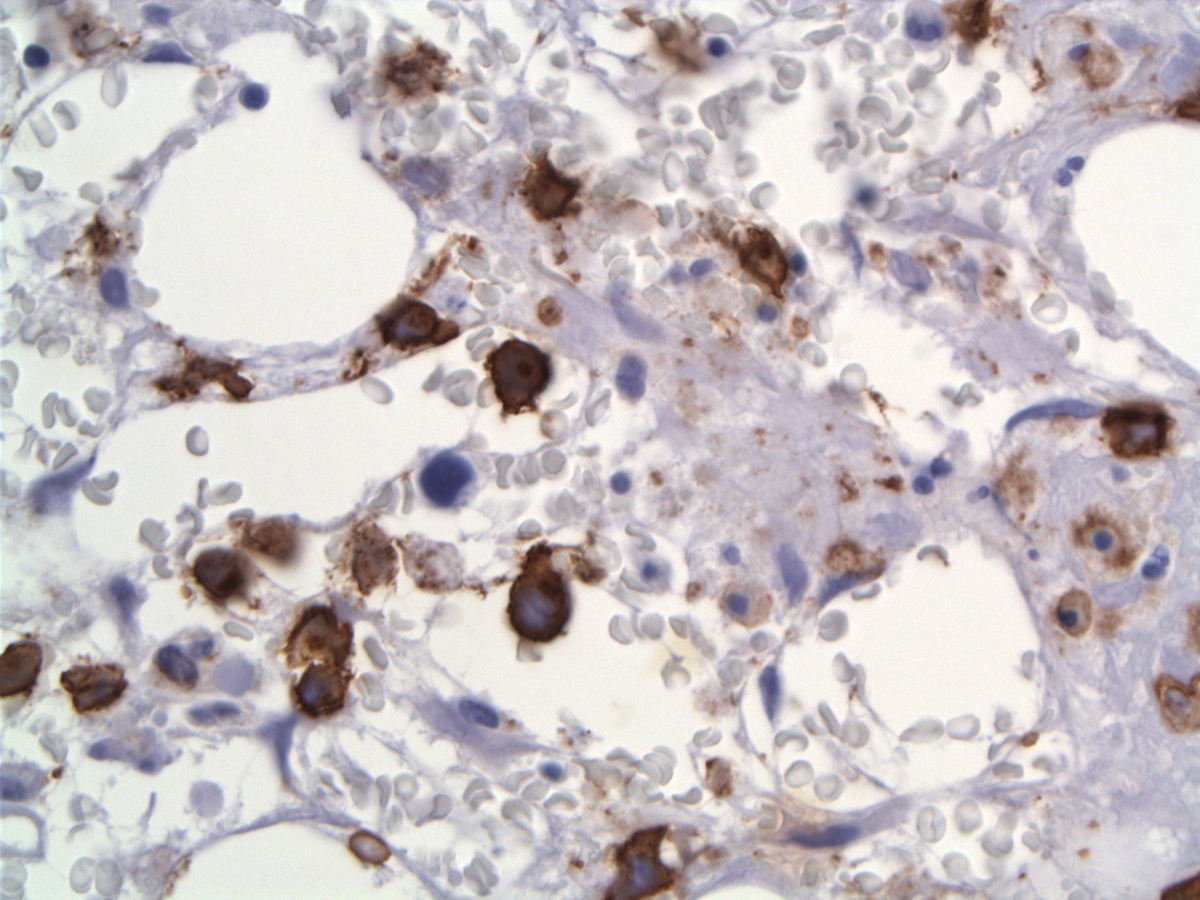

By immunohistochemistry, tumor cells were positive for CD30 (strong, diffuse, membranous and Golgi pattern), CD3, CD7 (weak, subset), CD45, CD8 (small subset), Beta F1 (weak), EMA (subset), TIA-1, Granzyme B, perforin and negative for CD5, CD15, CD20, CD34, CD123, TDT, ALK1, PAX5, CD68, EBV-LMP and EBER. No lymphoid aggregate or sinusoidal pattern of involvement were seen. CD68-positive histiocytes were increased but only rare cells showed evidence of hemophagocytosis. FCM detected an abnormal population expressing CD2, CD3, CD7, CD8, CD30, CD45bright, CD45RA, CD45ROhet while negative for CD4, CD5, CD13, CD16, CD33, CD34, CD56 and CD57. Review and additional studies with the earlier biopsy revealed interval decreased cellularity and presence of CD30+ lymphoma cells in that sample

| CD30 | ![]() |

| CD30 labels the neoplastic cells with membranous and Golgi pattern | ![]() |